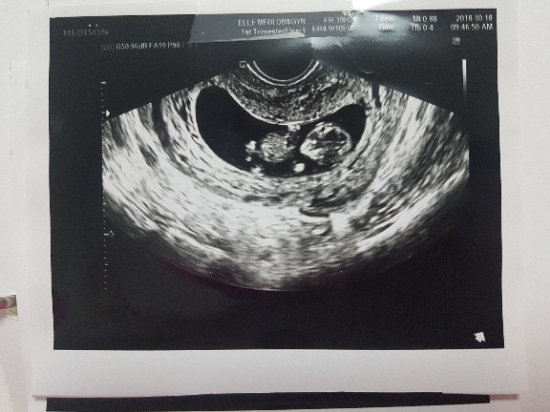

넷째 사등이 초음파사진

작년 9월 사등이가 찾아온걸알았지. 혹시나 혹시나해서 사진 안올렸는데 밀린사진 올려야지ㅋㅋ 9주6일 곰...